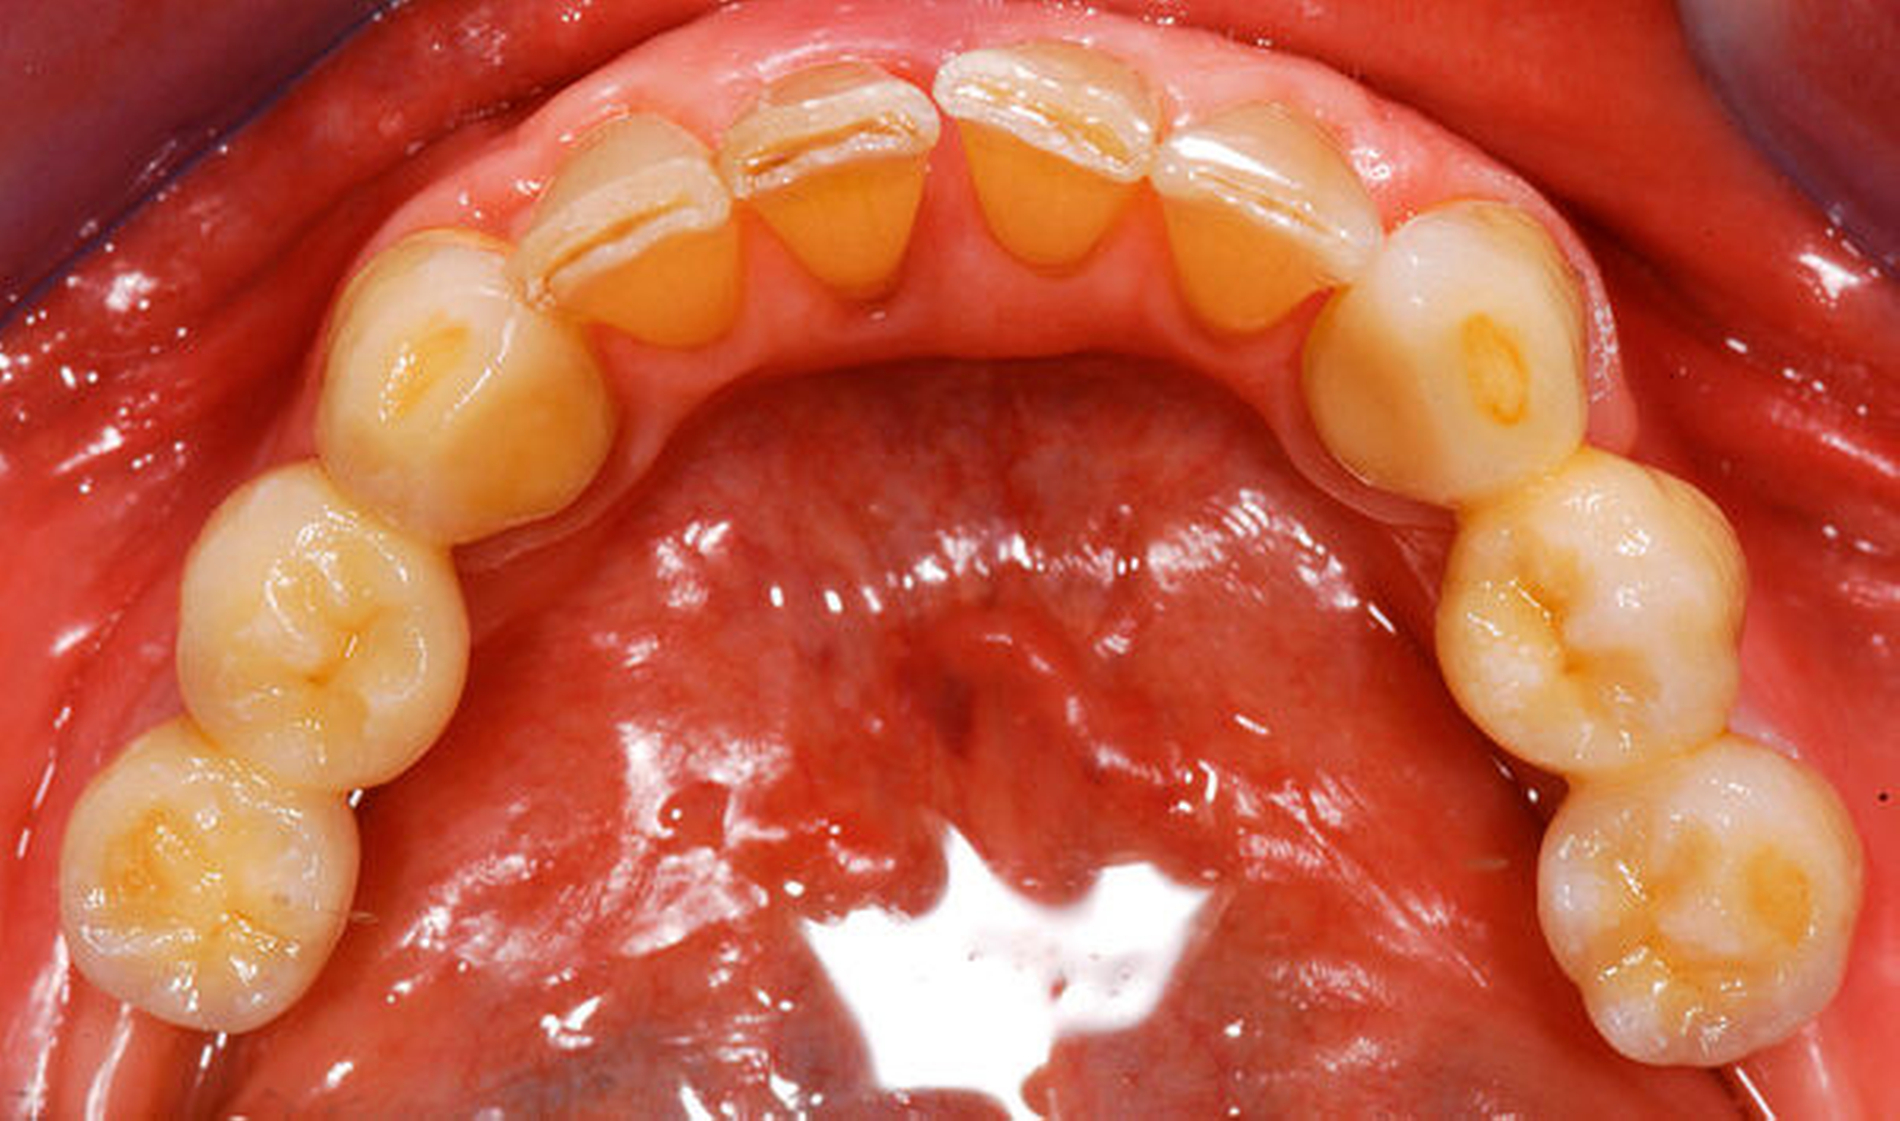

Bei der Rehabilitation von posterior verkürzten Zahnreihen zeigten Verbundbrücken aus verblendeten Zirkonoxidgerüsten nach drei Jahren eine Überlebenswahrscheinlichkeit von 93,9 Prozent (Abbildungen 1 bis 3). Im Rahmen von verschiedenen Studien wurden Überlebensraten für metallbasierte Verbundbrücken nach fünf Jahren zwischen 91,6 und 97,6 Prozent angegeben [Koth et al., 1988; Nickenig et al., 2006; Pieralli et al., 2018], nach zehn Jahren zwischen 81,7 [Mundt et al., 2012] und 87,8 Prozent [Nickenig et al., 2008]. In retrospektiven Untersuchungen, die explizit aus der Analyse der Daten für diese Leitlinie ausgeschlossen wurden, wird von Überlebensraten von bis zu 100 Prozent nach sechs Jahren berichtet [von Stein-Lausnitz et al., 2019].